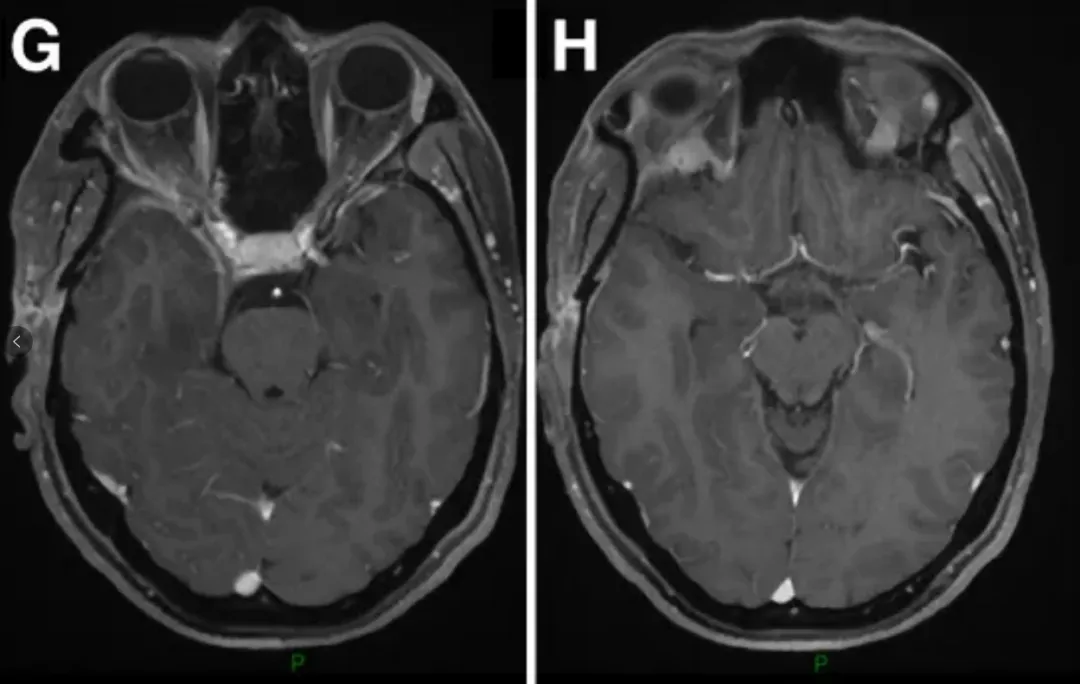

E-H:术后轴位MR图像显示肿瘤完全切除。